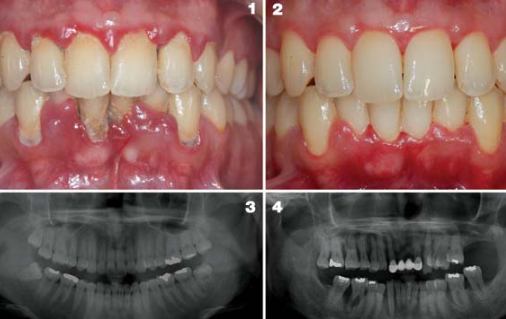

치아 건강을 이야기할 때 많은 사람들이 충치만 떠올리지만 실제로 치아를 잃게 되는 가장 큰 원인은 바로 잇몸질환입니다. 잇몸이 약해지면 치아를 지탱하는 뼈까지 손상될 수 있어 조기 관리가 매우 중요합니다.

특히 잇몸질환은 초기에 통증이 거의 없어 방치하기 쉽지만, 시간이 지나면 잇몸 출혈과 치아 흔들림으로 이어질 수 있습니다.

잇몸질환은 치아 주변 조직에 염증이 생기는 질환을 말합니다. 대표적으로 치은염과 치주염으로 나눌 수 있습니다.

| 치은염 | 잇몸에만 염증이 있는 초기 단계 | 잇몸 붓기, 칫솔질 시 출혈 |

| 치주염 | 잇몸뼈까지 염증이 진행 | 잇몸 내려앉음, 치아 흔들림 |

| 중증 치주염 | 치아 지지 조직 손상 | 치아 상실 가능 |

초기에는 가벼운 염증이지만 치료하지 않으면 치아 상실로 이어질 수 있습니다.